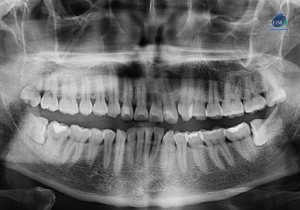

Paciente masculino de 50 años acude al Instituto de Diagnóstico Maxilofacial con el motivo de consulta de una tomografía de haz cónico de campo reducido